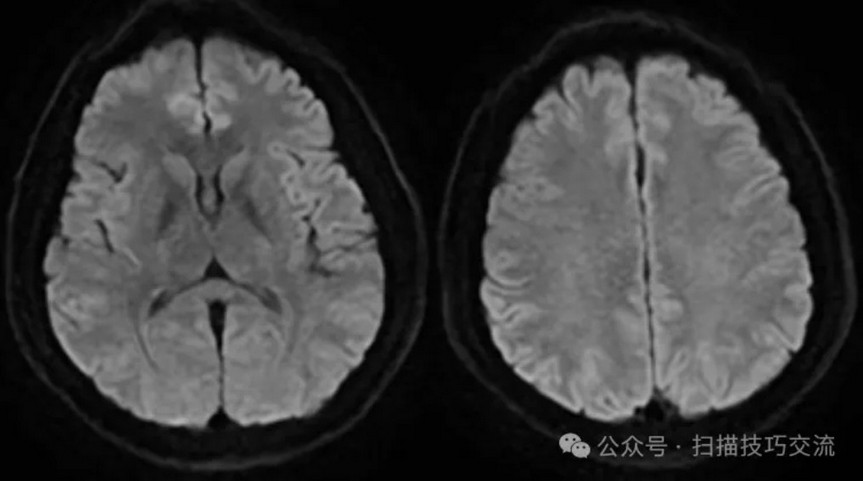

SWAN未见异常。